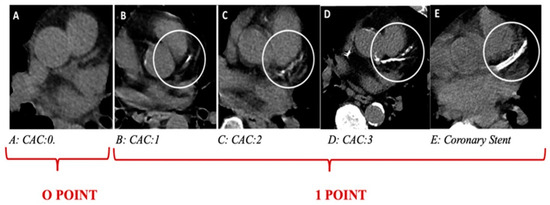

| Thorax CT-CACS | 3.5 (1–6.7) | 0 (0–3) | <0.001 |

| Thorax CT-CACS +, n (%) | 84 (%81) | 100 (%45) | <0.001 |

| Thorax CT CAC + aortic calcification + | 5.28 | 3.13–8.91 | <0.001 | 3.85 | 1.69–8.78 | 0.001 |

| C | CACS + Aort calcification + | 1 point |